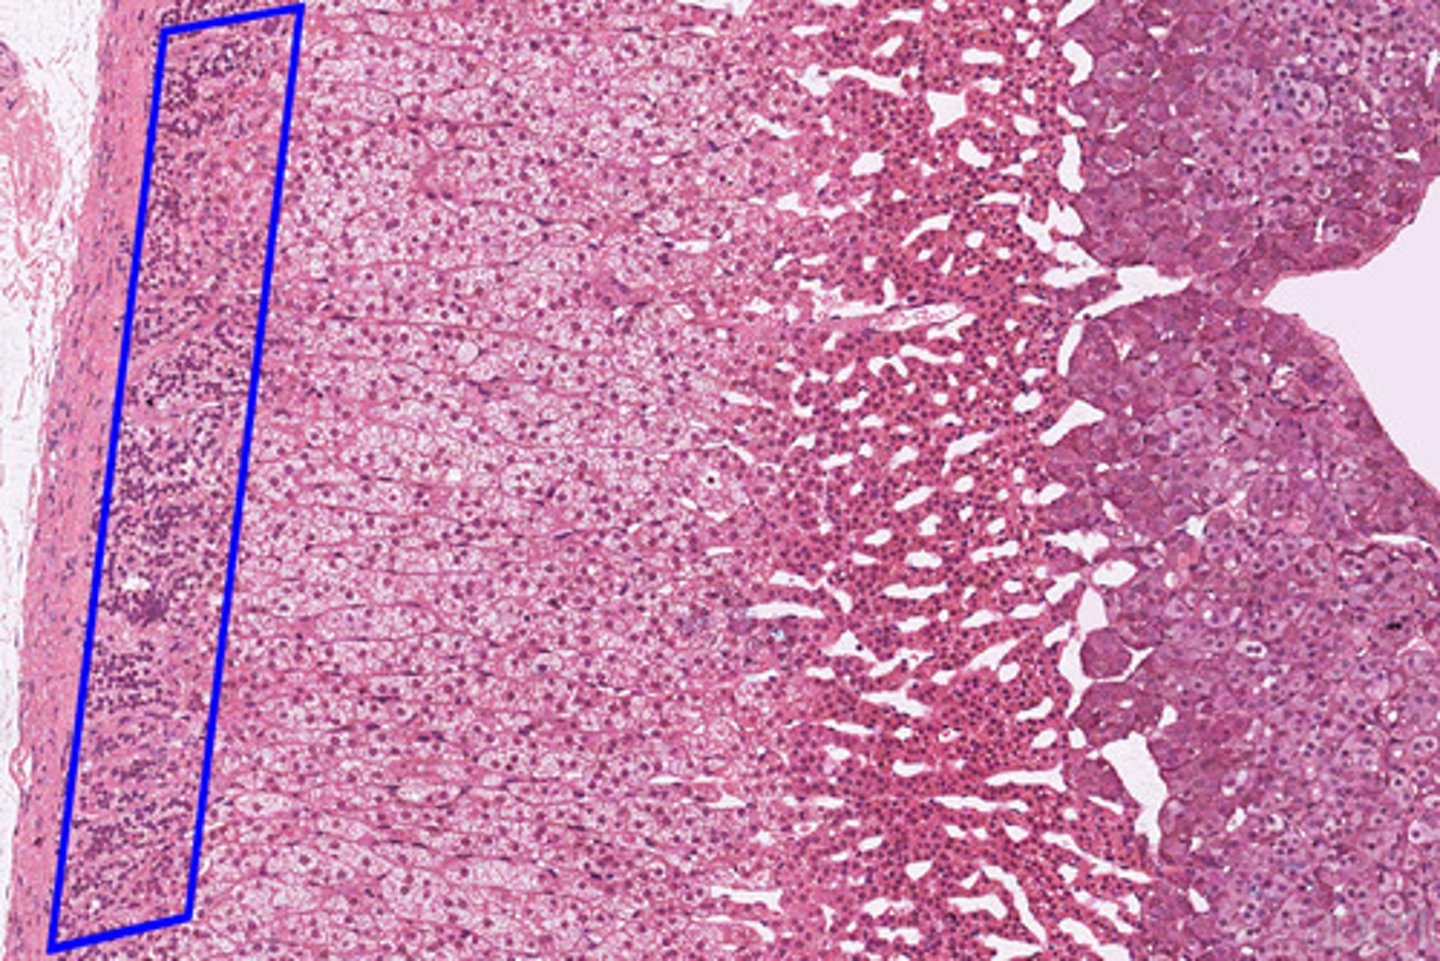

Adrenal gland

Adrenal cortex

Zona glomerulosa

Zona fasciculata

Zona reticularis

Adrenal medulla